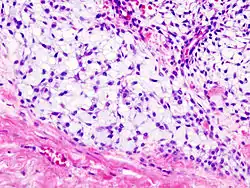

Histopathology

Imaging studies - including radiographs ("x-rays"), computerized tomography (CT), and magnetic resonance imaging (MRI) - are often used to make a presumptive diagnosis of chondrosarcoma.[11] However, a definitive diagnosis depends on the identification of malignant cancer cells producing cartilage in a biopsy specimen that has been examined by a pathologist. In a few cases, usually of highly anaplastic tumors, immunohistochemistry (IHC) is required.